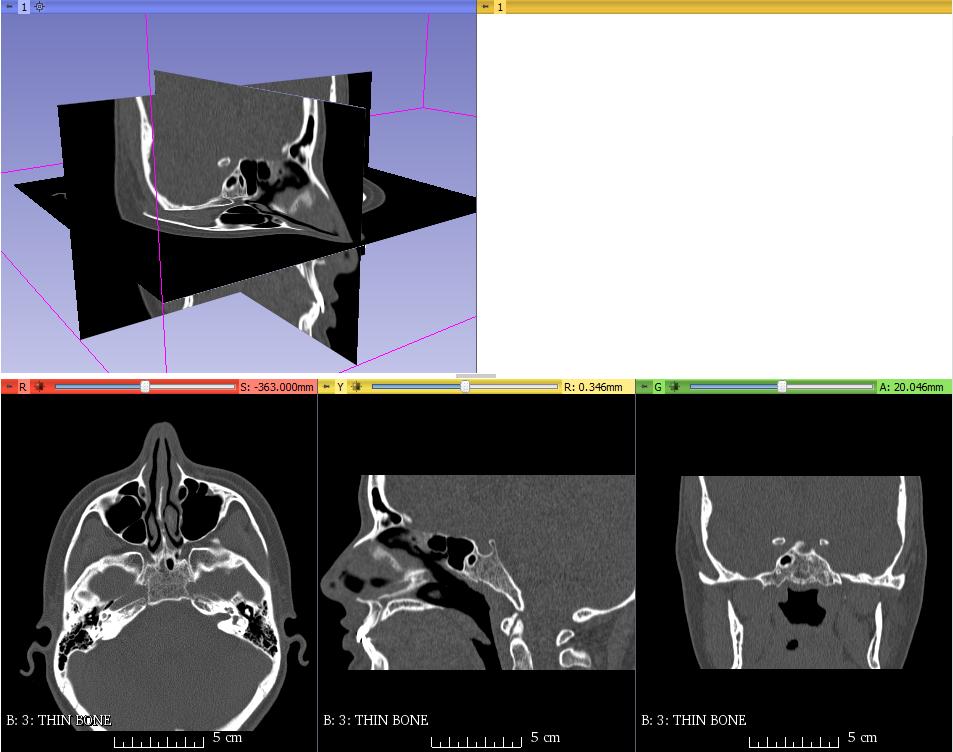

Using 3D Slicer, I extracted the data into an STL file. This program took each image and fused together the dense areas (bone), giving me a full model of the skull. Being constructed from such high-resolution data, the resulting STL was a massive file, and my computer did not enjoy working with it.

Using Autodesk Meshmixer, I simplified the STL by smoothing over some rough areas, and reducing the triangle count. This made the model much easier to load and slice for 3d printing.